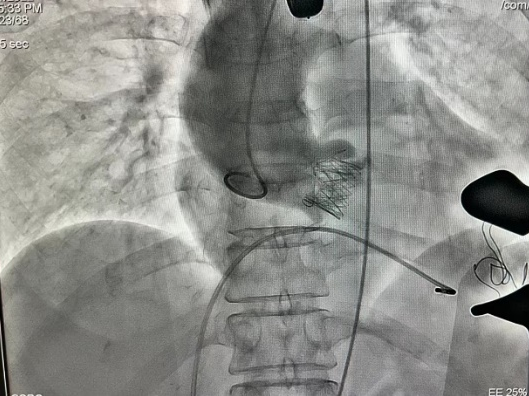

Case 1 患者为横位心重度返流,左锁骨下动脉-主动脉弓动脉瘤,降主动脉走形迂曲,胸-腹主动脉成角64度,左室流出道有凸出。经股入路成为禁忌,情况十分艰险。但在团队充分的术前准备和完整的手术策略支持下,成功经心尖植入一枚J-Valve介入瓣膜,完成了救治,患者获益良好。

Case 2 二叶瓣畸形病人,横位心,重度钙化伴返流,左室流出道重度钙化且伴有凸出,EF只有30%。安医大一附院TAVR团队凭借丰富的手术经验,默契配合,成功完成手术,术后造影显示,瓣膜位置立项,极轻微瓣周漏,冠脉血流通常。